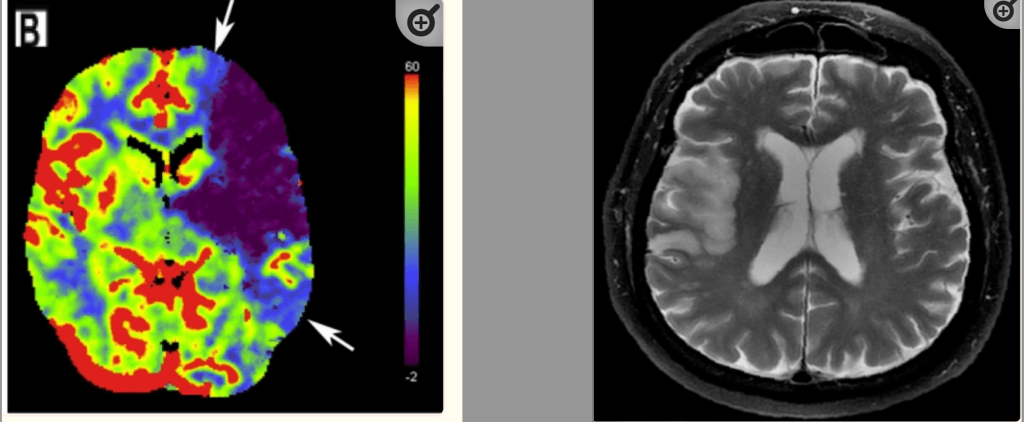

For example, a patient presenting with chest pain has findings on a chest x-ray that that could be pneumonia or pulmonary edema. Should they be treated for both, either, or neither? Or as another example, a patient with vague abdominal pain, a non-specific physical exam, and normal labs has a CT scan of the abdomen which shows findings of an adrenal mass or a marginally dilated appendix. Is the marginally dilated appendix the source of her symptoms? Should she be referred to the general surgeon for the marginally dilated appendix? What does adrenal mass mean for this patient? Does it require surveillance? Or the known scourge to the ED physician – the elderly patient with the interoceptive sensation of “dizziness.” Exam findings in such patients are reliably unreliable. Essentially grasping for security, the ED physician reaches for CT imaging to rule-out a high-morbidity diagnosis such as a brain hemorrhage, but knows full well that the test is insensitive to an ischemic stroke or a transient ischemic attack (TIA). If the CT happens to be normal and even if symptoms normalize, is the patient safe for discharge when neither an ischemic stroke or TIA is ruled-out?